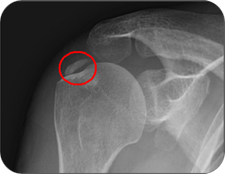

![]()

엑스레이 사진에서 어깨주변에 뼈 음영과 비슷한 밀도의 하얀 석회가 관찰됩니다.

석회의 위치에 따라 전후면, 측면 및 액와(겨드랑이) 엑스레이 사진에서 보입니다. 양측에 발생하는 경우도 있습니다. |